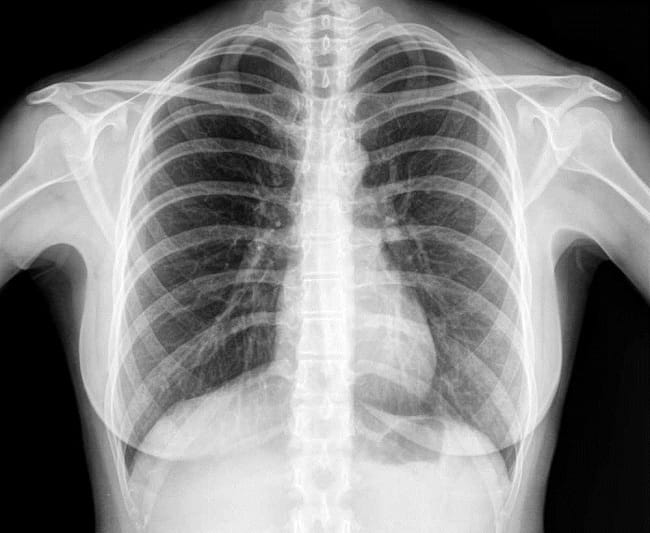

Namun, terkadang pemeriksaan x-ray juga digunakan untuk mendeteksi masalah kesehatan pada jaringan lunak dan organ dalam tubuh. Oleh karena itu, x-ray juga dapat dimanfaatkan untuk memeriksa paru-paru, payudara, jantung, dan saluran kemih maupun pencernaan. Rontgen juga sering dilakukan pada bagian dada dan perut.

Sebagian besar partikel x-ray tidak dapat menembus logam atau bagian tubuh yang padat, seperti tulang. Oleh karena itu, tulang atau logam akan berwarna putih pada hasil foto x-ray. Tumor juga biasanya akan tampak berwarna putih pada hasil foto x-ray.

Jaringan lunak, seperti darah, kulit, lemak, dan otot, akan berwarna abu-abu pada gambar pemeriksaan x-ray. Sementara itu, warna hitam menandakan x-ray mengenai udara atau gas.